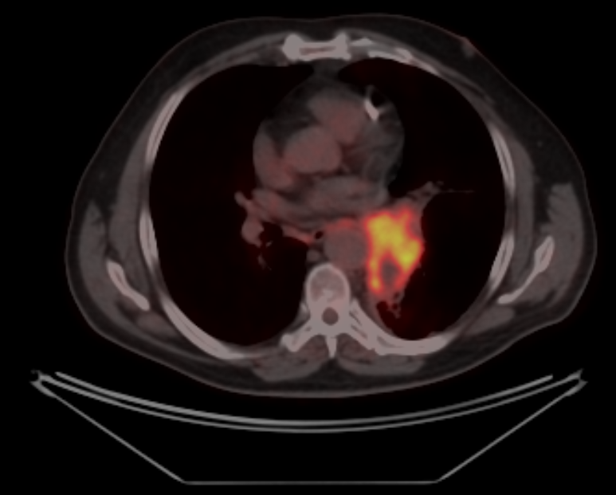

На момент исследования ПЭТ-КТ с 18F-ФДГ от 3.02.2023, в сравнении с ПЭТ-КТ от 18.10.2022г. отмечается дальнейшее уменьшение размеров со снижением уровня патологического метаболизма РФП ранее выявленного образования корня левого лёгкого; внутригрудные лимфатические узлы не увеличены, без патологического метаболизма РФП.Отмечается появление зон фиброза и инфильтрации легочной паренхимы с обеих сторон, с гиперметаболизмом РФП – вероятно как проявление постлучевого пневмонита – рекомендован КТ-контроль ОГК.